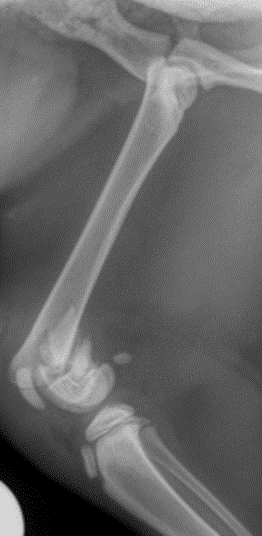

On trouve les cartilages de croissance chez les chats de moins d’un an, aux extrémités des os des pattes. Les cartilages de croissance permettent la croissance des os. Les cartilages de croissance sont plus fragiles que l’os proprement dit, et de ce fait plus souvent sujets aux traumatismes.

Les cartilages de croissance se ferment ou fusionnent à l’âge adulte. La majorité de la croissance de la plupart des chats se réalise entre 4 et 8 mois. Plus l’animal est de petit format plus sa croissance s’arrêtera tôt. Après 8 mois, la croissance se poursuit mais plus faiblement. A un an, les cartilages de croissance sont fermés et ne sont généralement plus visibles radiographiquement.

Parfois, une partie du cartilage reste fonctionnel et le traumatisme de celui-ci peut entrainer une croissance anormale. L’axe de l’os est modifié car une partie du cartilage de croissance va continuer à grandir mais pas l’autre. Cela peut entrainer des déformations du membre handicapantes.